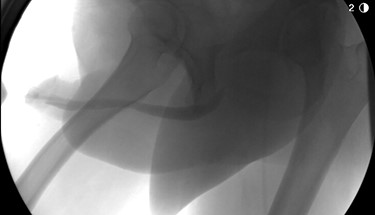

Given the mild nature of his symptoms, the patient initially refused surgical intervention and had been managed with intermittent urethral stricture dilatation. Eventually, the patient elected to proceed with definitive surgical management. He underwent anterior urethroplasty utilizing an excision and primary anastomosis approach which was completed successfully and without complication. Final pathology of the excised diseased segment confirmed amyloidosis without evidence of malignancy. Follow up RUG demonstrated a well-healed anastomosis without leak and excellent urethral patency (Fig. 3). At the latest follow up of 6 months, the patient continues to do well and denies lower urinary tract symptoms or hematuria.

Postoperative imaging demonstrating a well-healed urethral anastomosis with excellent patency.